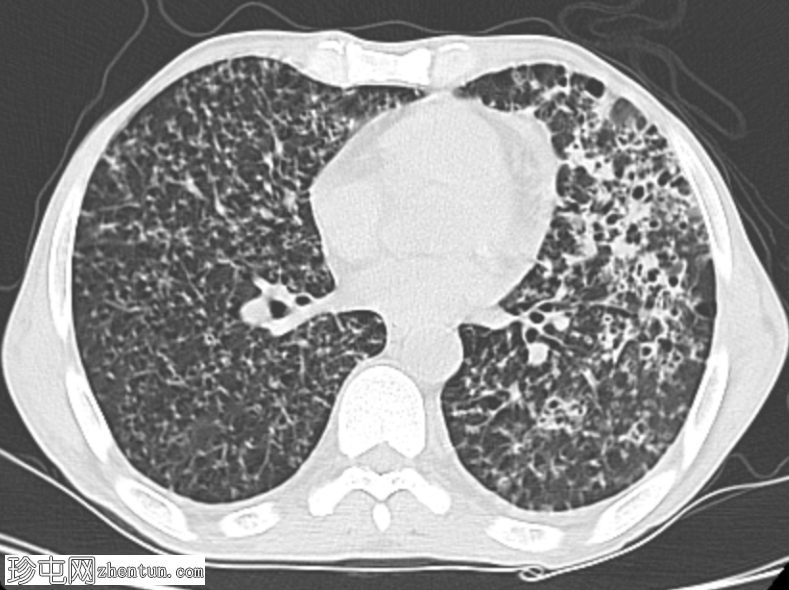

CT扫描图像:双侧肺部广泛粟粒性结节。

双侧肺部广泛粟粒性结节及树芽征,伴左上叶空洞及小气腔实变。